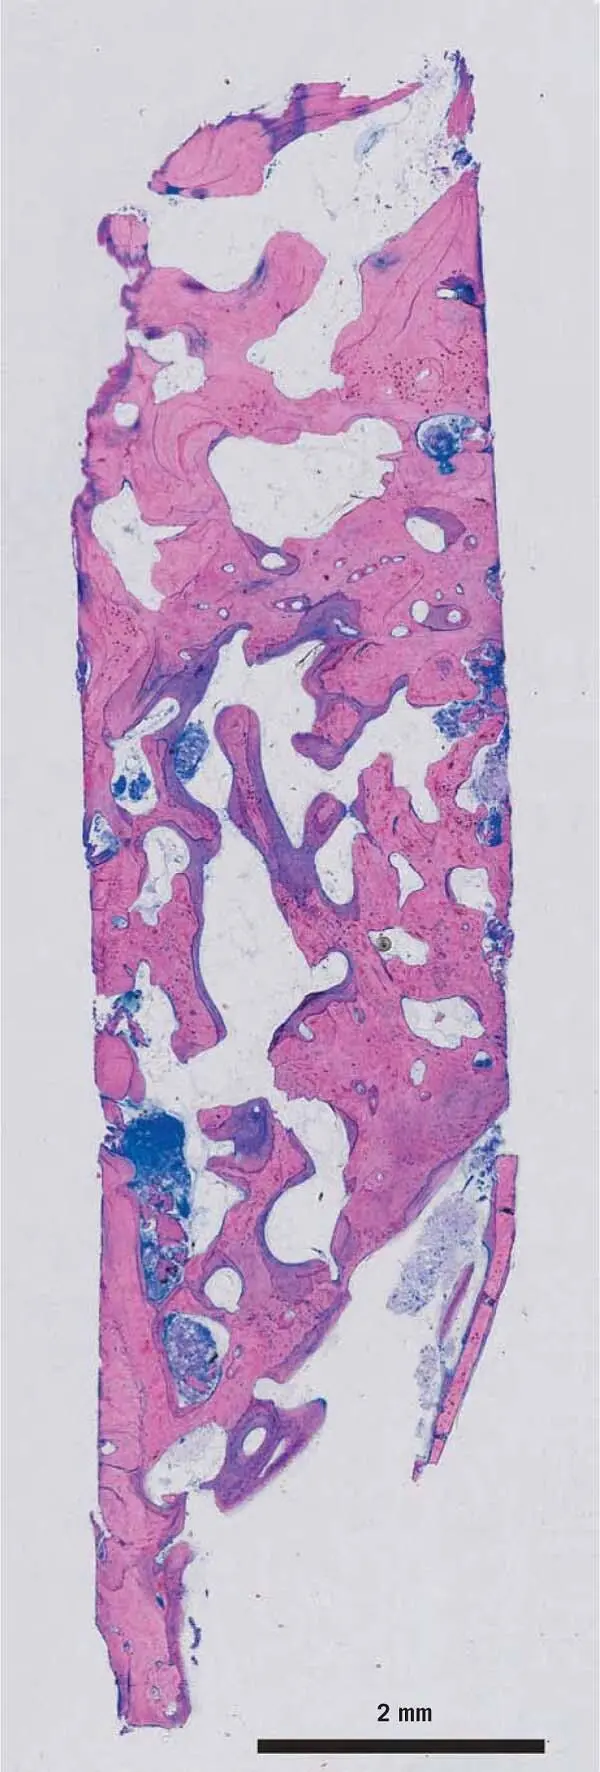

Fig 19Biopsy from the split bone block SBB technique The space between the - фото 12

Fig 1-9Biopsy from the split bone block (SBB) technique. The space between the thin bone blocks and the remaining alveolar crest was filled with the scraped autogenous bone chips. After 3 months, the implants were inserted in the grafted area. 70,72After 3 months of healing, bone cores from the planned implant site were removed for histology. In this image, the new bone is stained purple, while the old pristine bone and the transplanted bone chips are pink.